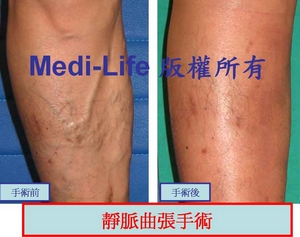

<案例一>

嚴重的靜脈曲張亦是可以輕易解決

嚴重的靜脈曲張亦是可以輕易解決